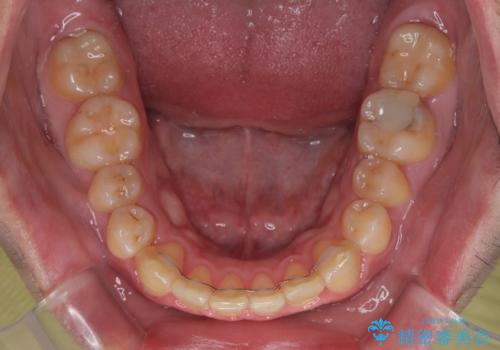

上顎前歯のデコボコを改善してスッキリした口元に ワイヤー装置での非抜歯矯正

- 上顎前歯のデコボコを気にして来院された患者様です。

上下前歯にデコボコがありましたが、特に上顎の叢生が強く、通常に歯列を整えると、上顎が前方に突出し、口元の突出感が残った仕上がりとなる可能性が考えられました。

非常に咬合力が強く、左側の臼歯がなかなか後方へ移動できなかったのですが、2年ほどかけて大変満足のいく仕上がりを達成することができました。